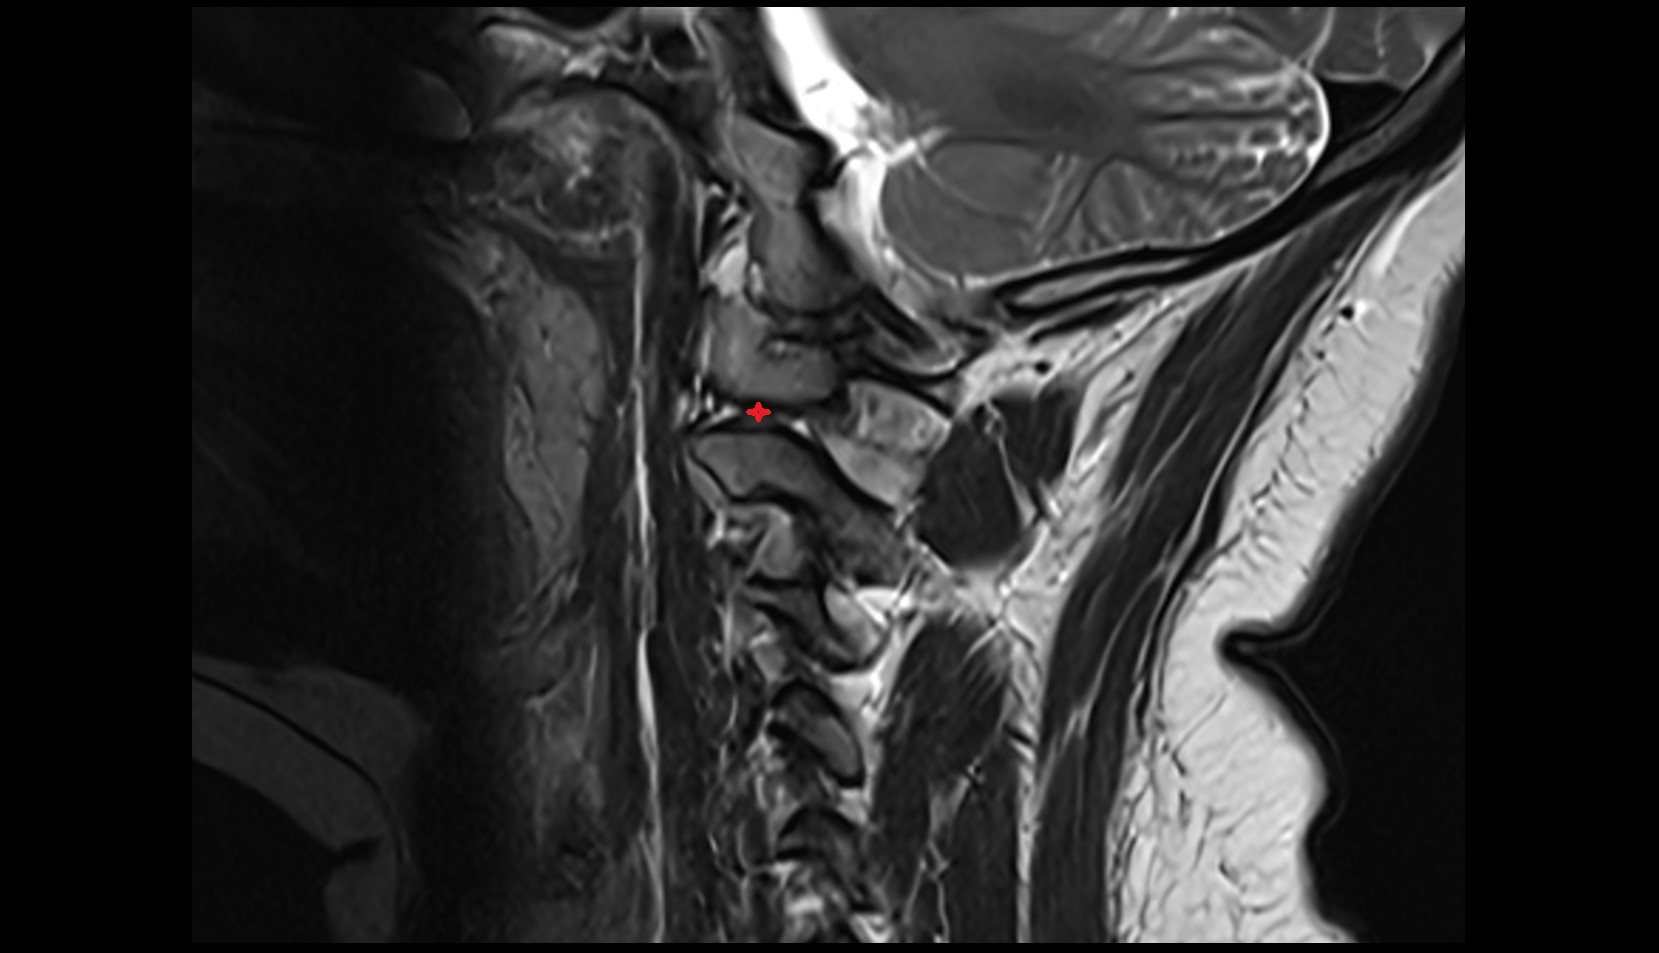

- Upper cervical spinal cord

- Axis (C2 vertebra)

- C3–C4 intervertebral disc

- Anterior longitudinal ligament

- Posterior longitudinal ligament

- Ligamenta flava (Ligamentum flavum)

- Spinal cord

- Cisterna magna